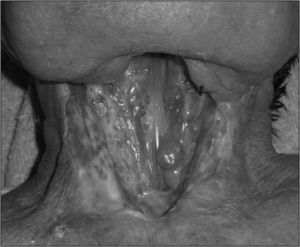

ResultadosObservamos que la extensión de la cirugía a la faringe es el único factor asociado significativamente (p=0,04) a la aparición de fístulas en nuestro medio (odds ratio [OR] = 2,83). La asociación de radioterapia previa y vaciamientos cervicales muestra una tendencia importante (OR = 3,2), no significativa (p=0,099). Otros factores como la edad del paciente, la radioterapia previa, los vaciamientos cervicales, la traqueotomía previa o la hemoglobina postoperatoria no se asocian estadísticamente a la aparición de esta complicación. La mayoría de las fístulas se cierran con medidas conservadoras (72,7 %), pero en pacientes irradiados previamente requieren reparación quirúrgica con mayor frecuencia que en los no irradiados (p <0,01).

ConclusionesEn nuestro medio el factor más asociado a la aparición de fístulas tras laringectomía es la extensión de la cirugía a la faringe. Las fístulas en pacientes irradiados tienen menor tendencia a la reparación conservadora y requieren cirugías más agresivas para solucionarlas.

ResultsThe only risk factor with statistical significance (P=.04) for the onset of fistulae in our setting is the extension of the surgery to the pharynx (OR=2.83). The association of prior radiotherapy and concurrent neck dissection displayed a notable trend (OR=0.32) but without significance (P=.099). Patient age, prior radiotherapy, concurrent neck dissection, prior tracheotomy and post-operative haemoglobin level did not predispose to this complication in our study. Non-surgical closure of the pharyngocutaneous fistula was achieved in most cases (72.7 %) but patients who had pre-operative radiotherapy required surgical closure more frequently (P<.01) than those not irradiated.

ConclusionsAt our centre the main risk factor associated with post-laryngectomy fistulae is the extension of surgery to the pharynx. In previously-irradiated patients, fistulae have a lower incidence of non-surgical closure and require more aggressive surgery to resolve them.